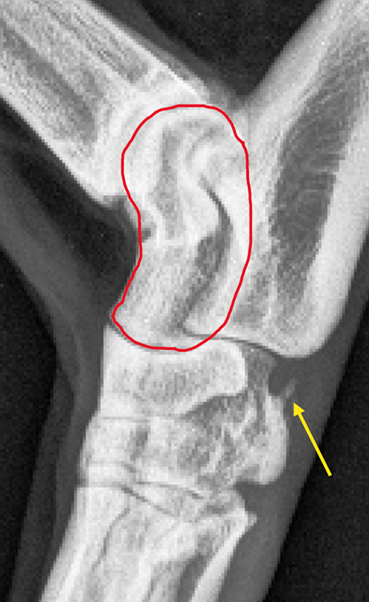

(A) PRE-FRACTURE

Lateral X-Ray of hock (Before)

• Yellow arrow points to calcification in the plantar ligaments. The laying down of calcium in soft tissues happens in response to over-stretching however structural flexibility is now reduced.

• Red outline on the talus which is the bone that pounds down onto the CTB - the common fracture site.

This dog raced successfully for 4 months before rupture of the calcified plantar ligament seen in the X-Ray above.